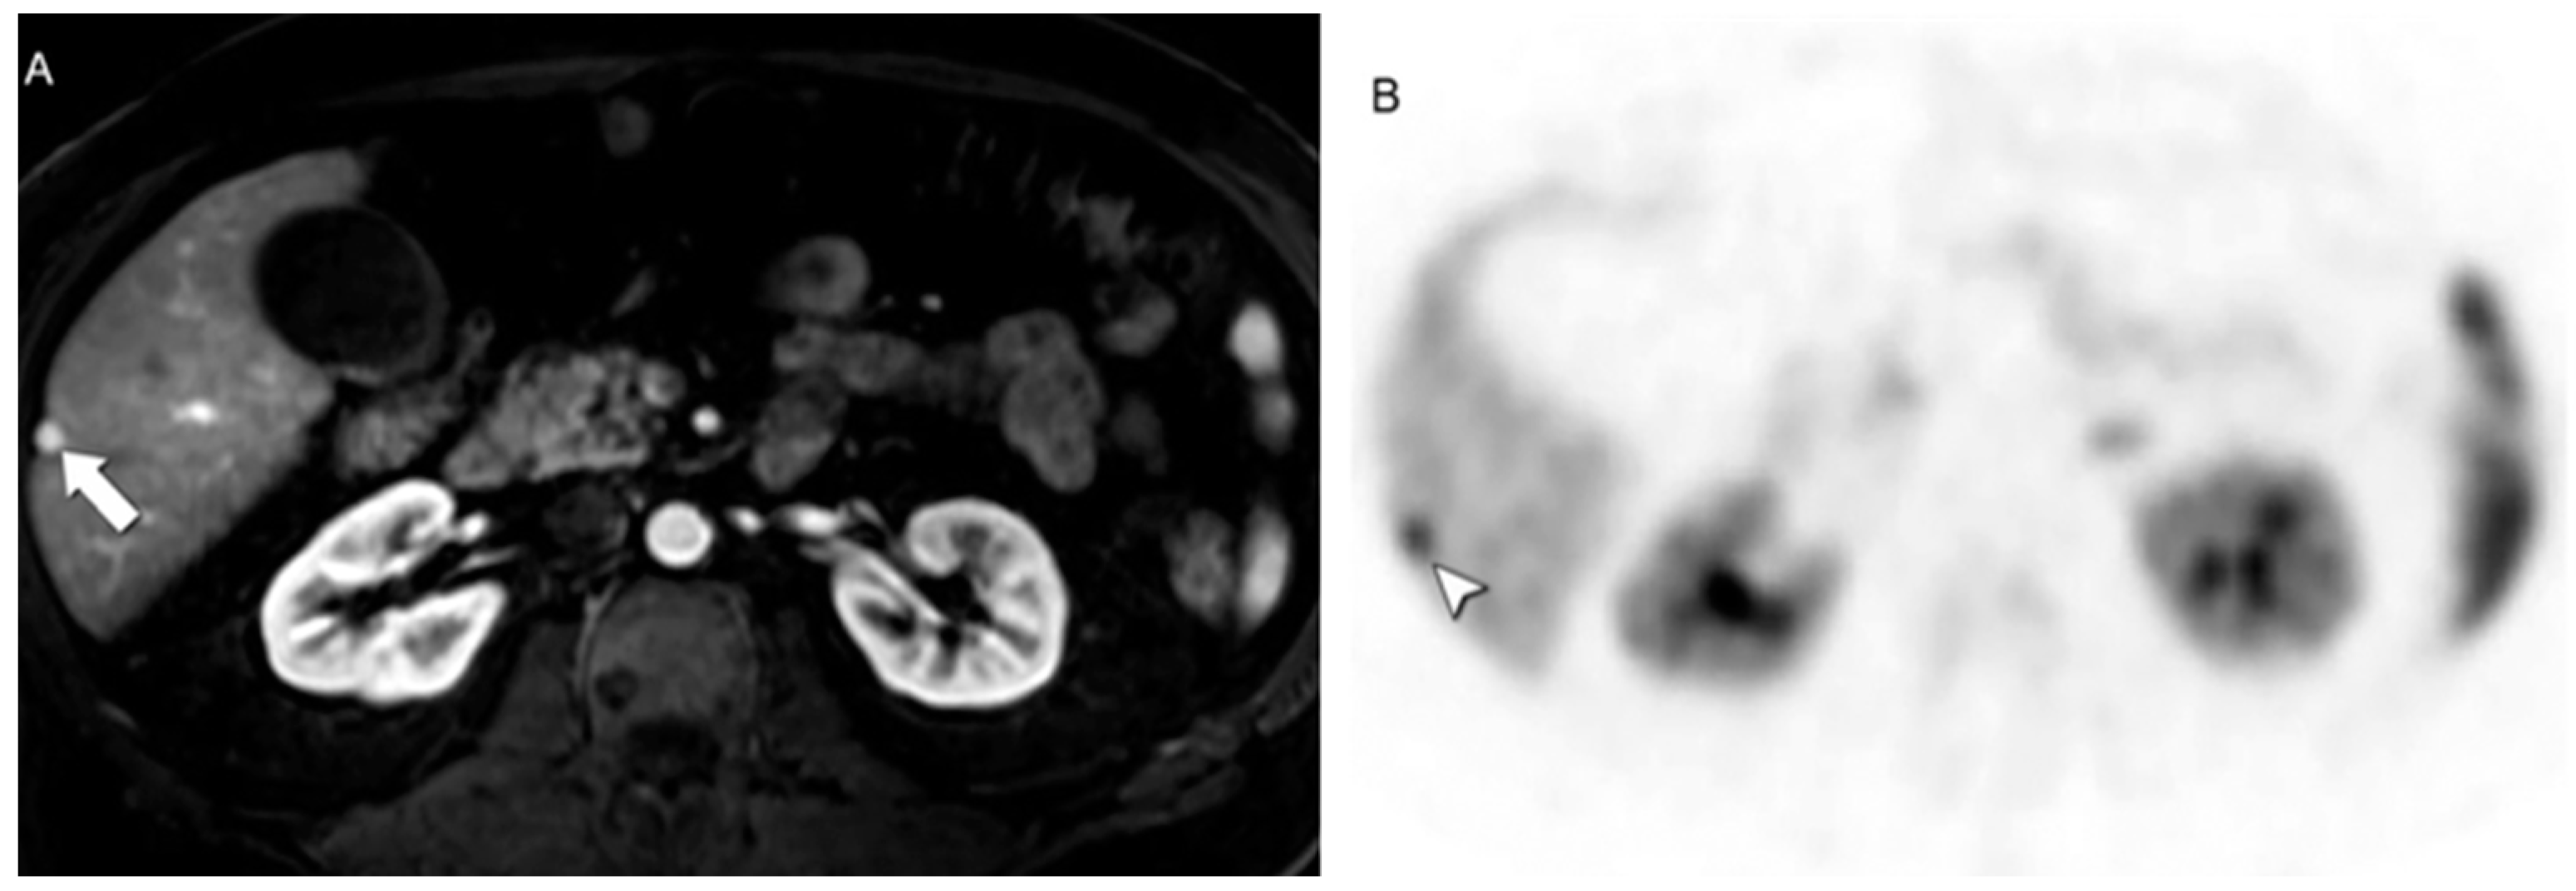

- Tirumani, S.H.; Jagannathan, J.P.; Braschi-Amirfarzan, M.; Qin, L.; Balthazar, P.; Ramaiya, N.H.; Shinagare, A.B. Value of Hepatocellular Phase Imaging after Intravenous Gadoxetate Disodium for Assessing Hepatic Metastases from Gastroenteropancreatic Neuroendocrine Tumors: Comparison with Other MRI Pulse Sequences and with Extracellular Agent. Abdom. Radiol. 2018, 43, 2329–2339. [Google Scholar] [CrossRef] [PubMed]

- d’Assignies, G.; Fina, P.; Bruno, O.; Vullierme, M.-P.; Tubach, F.; Paradis, V.; Sauvanet, A.; Ruszniewski, P.; Vilgrain, V. High Sensitivity of Diffusion-Weighted MR Imaging for the Detection of Liver Metastases from Neuroendocrine Tumors: Comparison with T2-Weighted and Dynamic Gadolinium-enhanced MR Imaging. Radiology 2013, 268, 390–399. [Google Scholar] [CrossRef]